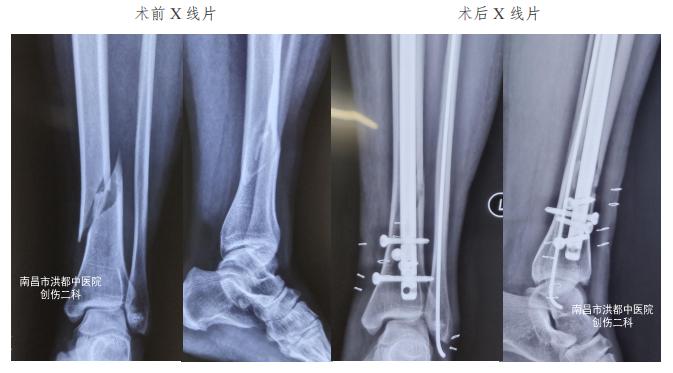

入院后,医生给阿莲的患肢予以石膏外固定,运用中药活血化瘀消肿止痛治疗。待完善相关检查,肿胀有所消退,在受伤后第5天,医生为阿莲行 胫腓骨骨折闭合复位髓内钉内固定术 。

术后第三天,阿莲即按医嘱,拄拐下地,左小腿部分负重行走。出院后,阿莲继续在医生指导下,开展康复训练,在确认骨折断断愈合后,恢复日常的自由活动,并逐步开始恢复性运动。

术前术后对比

创伤二科作为医院骨伤学科的老牌科室,对于各种骨折疾病有着丰富的治疗经验。本着微创、固定可靠和及早康复的治疗理念,该科 采用髓内钉内固定+阻挡钉技术的治疗方案 (图C), 达到切口小 (图D), 不干扰骨折端软组织血供,接近完美的骨折端复位、可靠内固定的治疗效果。